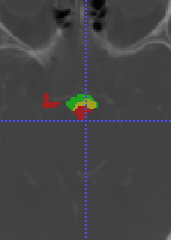

In Chapter 6, we propose an end-to-end, atlas-free 3D convolutional deep learning framework for fast and fully automated whole-volume HaN anatomy segmentation [115]. Our deep learning model, called AnatomyNet, segments OARs from head and neck CT images in an end-to-end fashion, receiving whole-volume HaN CT images as input and generating masks of all OARs of interest in one shot. AnatomyNet is built upon the popular 3D U-net architecture, but extends it in three important ways: 1) a new encoding scheme to allow auto-segmentation on whole-volume CT images instead of local patches or subsets of slices, 2) incorporating 3D squeeze-and-excitation residual blocks in encoding layers for better feature representation, and 3) a new loss function combining Dice scores and focal loss to facilitate the training of the neural model. These features are designed to address two main challenges in deep-learning-based HaN segmentation: a) segmenting small anatomies (i.e., optic chiasm and optic nerves) occupying only a few slices, and b) training with inconsistent data annotations with missing ground truth for some anatomical structures. We collect 261 HaN CT images to train AnatomyNet, and use MICCAI Head and Neck Auto Segmentation Challenge 2015 as a benchmark dataset to evaluate the performance of AnatomyNet. The objective is to segment nine anatomies: brain stem, chiasm, mandible, optic nerve left, optic nerve right, parotid gland left, parotid gland right, submandibular gland left, and submandibular gland right. Compared to previous state-of-the-art results from the MICCAI 2015 competition, AnatomyNet increases Dice similarity coefficient by 3.3% on average. AnatomyNet takes about 0.12 seconds to fully segment a head and neck CT image of dimension , significantly faster than previous methods. In addition, the model is able to process whole-volume CT images and delineate all OARs in one pass, requiring little pre- or post-processing. We demonstrate that our proposed model can improve segmentation accuracy and simplify the auto-segmentation pipeline. These contributions are released as an open-source software package called AnatomyNet, which is publicly available555https://github.com/wentaozhu/AnatomyNet-for-anatomical-segmentation. Portions of this chapter were published as part of [115].